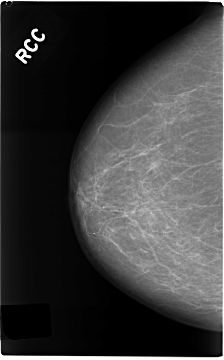

C_0146_1.RIGHT_CC

RIGHT_CC LINES 4672 PIXELS_PER_LINE 2904 BITS_PER_PIXEL 12 RESOLUTION 50 NON_OVERLAY